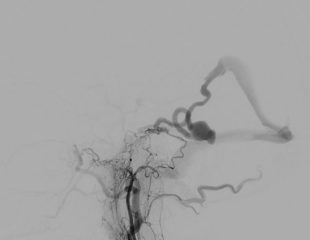

Successful brain tumour surgery for patient in her 30s using advanced Navigation technology Thursday, 02/04/2026

A woman in her 30s from Cambodia was admitted with numbness and a significant loss of motor function nearly 80%